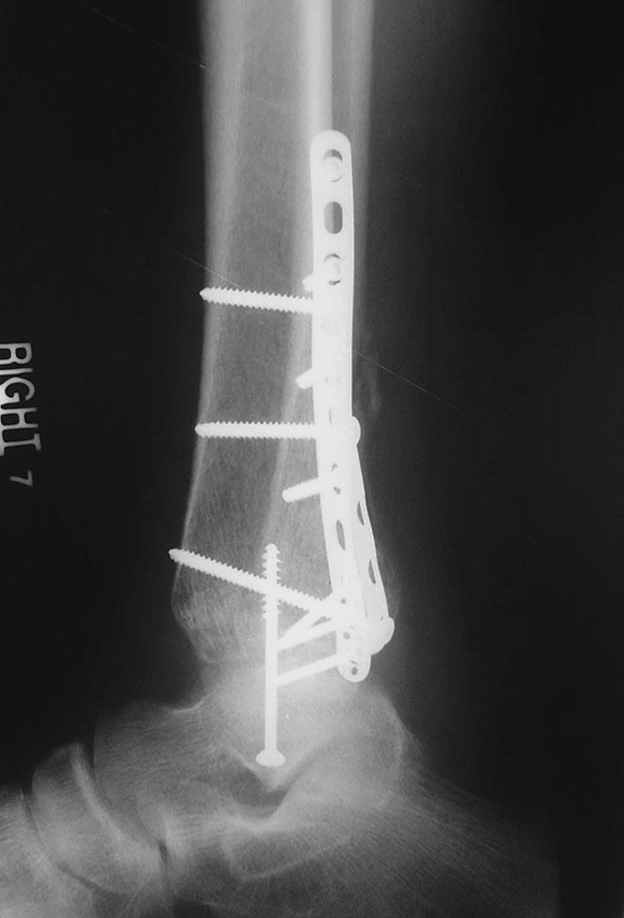

Re: ANKLE FRACTURE

Второй случай сделан из одного разреза

ЕЧ LISS plate, mininvasive approach - luxurous !

На прямой проекции послеоперационного Рг макроскопически все выглядит очень анатомично, при микроскопическом ( :-)) ) рассмотрении можно все-таки заметить вальгизацию тарана, суставная щель в латеральном отделе сустава несколько уже , чем в медиальном при отсутствии латерального смещения тарана. У меня был аналогичный случай (без LISS , без мини доступа) с вальгусным наклоном тарана при восстановленном ankle mortise при последовательном наблюдении с интервалами в 6-8 недель в послеоперационном периоде отмечалось прогрессирующее сужение суставной щели в латеральном отделе сустава, закончившееся посттравматическим ОА, к счастью боли умеренные, купируемые аналгетиками или своими эндорфинами:-))(активная пациентка, у которой нет времени на болезни....) Какова жизненная ситуация в приведенном вами случае? И последнее, что я хотел бы прояснить для себя - фиксация внутренней лодыжки: я обычно комбинирую фиксацию компрессирующим винтом со спицей - по идее ротационная стабильность должна быть лучше, чем один винт, каковы ваши наблюдения в этом плане?